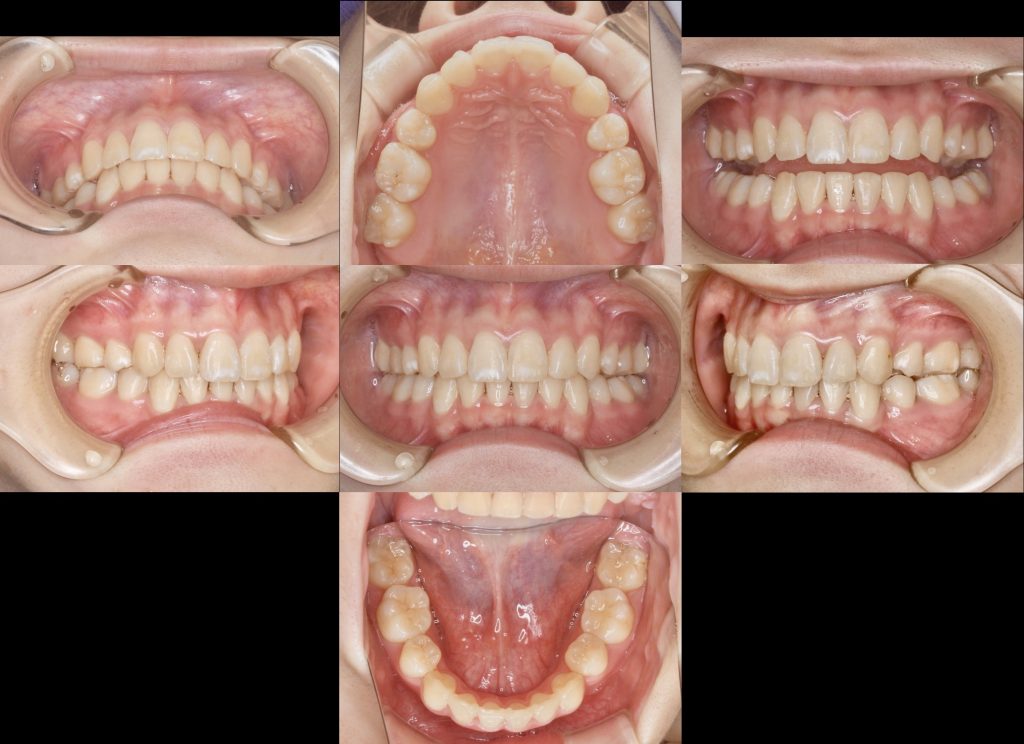

下記の症例は歯列不正(叢生)に対して、第一小臼歯を上下4本抜歯し、スペースクローズをワイヤー矯正にて行いました。

当医院では、必ず詳細な術前検査を行い、治療後の歯並び、噛み合わせ、骨格バランス、口唇との関係性、美しい側貌など多角的に診断し、治療方法、治療期間、費用をご説明しております。(矯正診断料は症例の難易度により10万円から30万円まで)

治療期間 2年6ヶ月

治療費用 約140万円(税抜き)